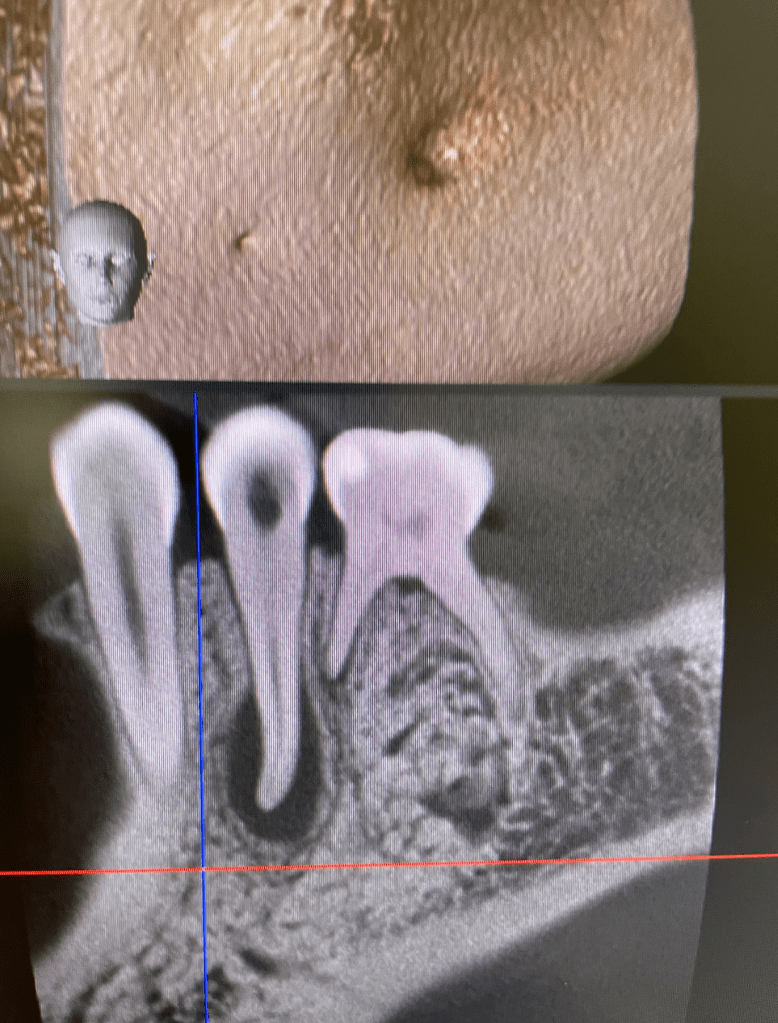

CALCIFICADOS

Premolar calcificado lesion